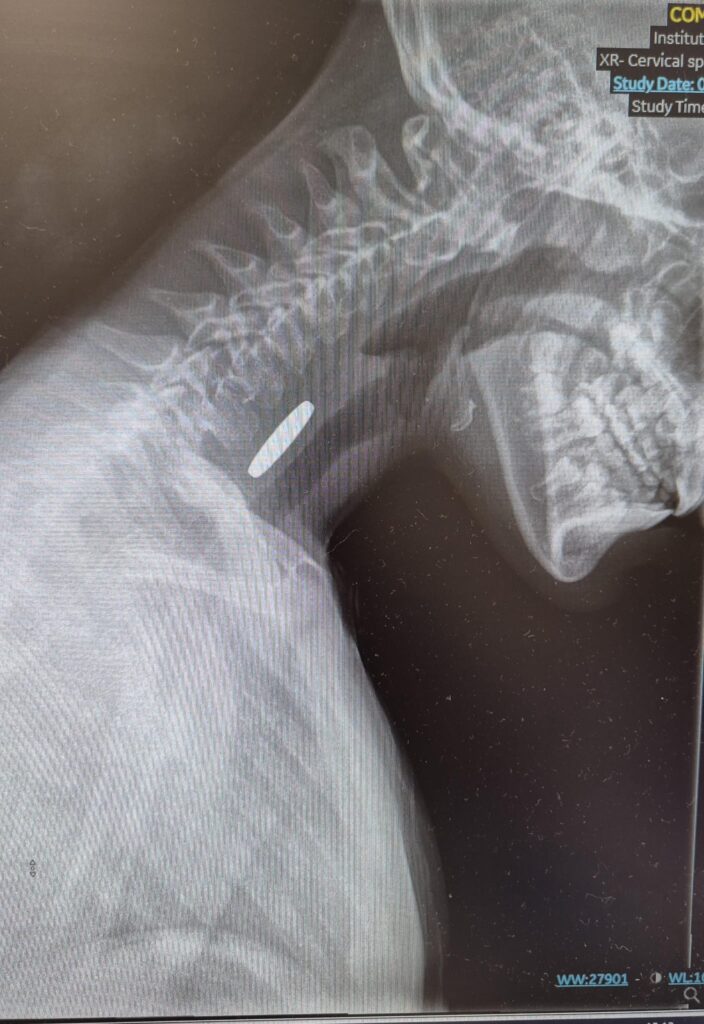

בשבוע האחרון הגיעו למלר"ד ילדים בבית החולים הציבורי אסותא אשדוד שתי ילדות, בנות 7 ו־10, לאחר שבלעו מטבעות כסף.

במקרה אחד, המטבע המשיך לקיבה; במקרה השני, נדרש ניתוח להוצאתו בשיתוף פעולה של מחלקת גסטרו-ילדים של ביה״ח.